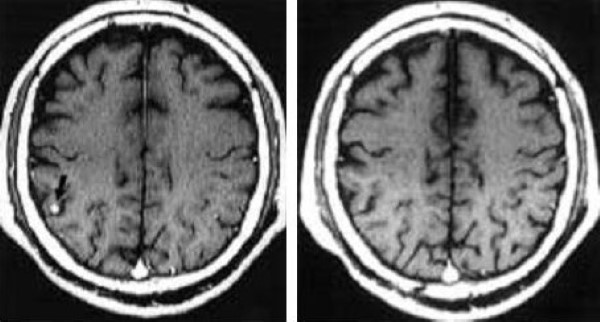

Đột quỵ thiếu máu cục bộ cấp có thể biểu hiện là một tổn thương não có giới hạn không rõ ràng, gây hiệu ứng khối, nhu mô tổn thương ngấm thuốc tương phản hoặc không [8]. Các dấu hiệu hình ảnh này tương tự với dấu hiệu của u thần kinh đệm (glioma). Trong các tình huống này, chụp cộng hưởng từ khuếch tán (diffusion-weighted imaging) có thể khá hữu ích, cho dù không nhất thiết để kết luận. Nếu không có cộng hưởng từ khuếch tán, việc phân biệt giữa đột quỵ thiếu máu cục bộ cấp và u não là khó ở các bệnh nhân không có tiền sử lâm sàng rõ ràng (Hình 1a và 1b). Theo dõi bằng hình ảnh trong một thời gian ngắn là cần thiết để chẩn đoán nhồi máu não trong các trường hợp này (Hình 1c và 1d) [8].

Hình 1 a/b. Glioma? Bệnh nhân nam 65 tuổi biểu hiện rối loạn dáng đi từ từ. (Chẩn đoán cuối cùng: nhồi máu não theo sự phân bố của động mạch vân trong).

a và b: MRI lúc nhập viện

a: một vùng tăng cường độ ở đầu nhân đuôi trái kéo dài tới phần trước của nhân vỏ sẫm trái trên ảnh FLAIR (TR/TI/TE 9000/2350/ 119) với một hiệu ứng khối ép sừng trán trái não thất bên. Vùng cường độ cao này phù hợp với sự phân bố của động mạch vân trong.

b: ảnh spin-echo (SE) T1-W (TR/TE 600/50) sau tiêm thuốc đối quang từ thấy tổn thương không ngấm thuốc. MR angiography (MRA)(không trình bày) bộc lộ tắc đoạn gần động mạch quặt ngược Heubner trái.

Hình 1 c/d: Chụp MRI 6 tuần sau

c: ảnh FLAIR (9000/2350/119) cho thấy sự co lại của vùng tăng cường độ ở phần trước của nhân nền trái. Sự chèn ép sừng trán trái đã biến mất.

d: ảnh SE T1-W (600/15) cho thấy tăng cường độ ở đầu nhân đuôi trái biểu hiện chảy máu.